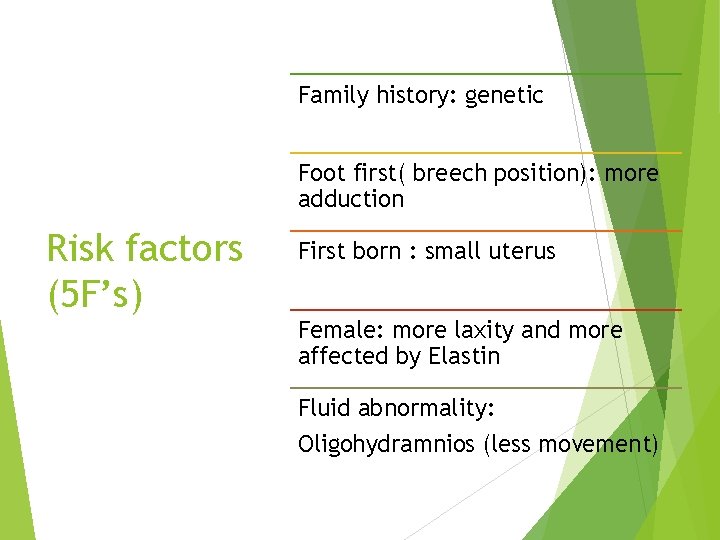

Family history: genetic Foot first( breech position): more adduction Risk factors (5 F’s) First born : small uterus Female: more laxity and more affected by Elastin Fluid abnormality: Oligohydramnios (less movement)

Post natal factor: Swaddling